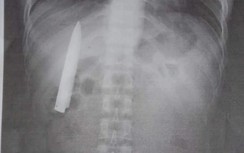

Mảnh xương cá sắc nhọn mắc ngang thực quản được gắp ra

Khi nội soi thực quản - dạ dày, ngoài phát hiện viêm dạ dày, các bác sỹ phát hiện có xương cá sắc nhọn mắc ngang thực quản, chiều dài xương khoảng 3 cm.

BS Lê Văn Khoa, Chuyên khoa Tiêu hóa của bệnh viện cơ sở 2 trực tiếp thăm khám bệnh nhân đã dùng kìm chuyên dụng để gắp dị vật. Ngay sau đó, bệnh nhân được kê đơn điều trị nội khoa.